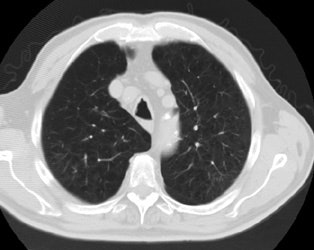

Positive lung cancer screening exam: The patient shown below had undergone lung screening CT in 2002 (left image). The patient was lost to follow-up, but returned for a repeat screening exam in 2007. The 2007 (right image) exam revealed a new stage I NSCLC in the right apex. There is a small linear scar in the medial left apex. |